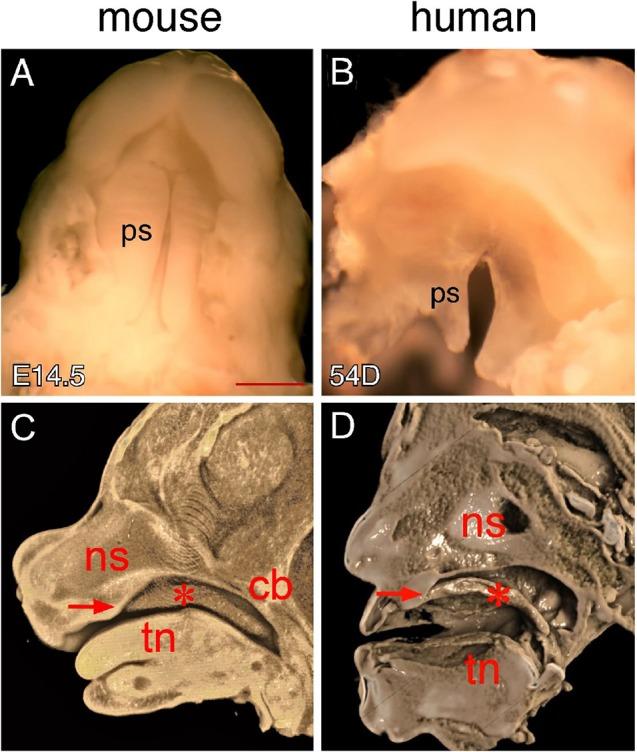

Differences in Oral Structure and Tissue Interactions during Mouse vs. Human Palatogenesis: Implications for the Translation of Findings from Mice.

Clefting of the secondary palate is one of the most common human birth defects and results from failure of the palatal shelves to fuse during embryonic development. Palatogenesis is traditionally considered to be a highly conserved developmental process among mammalian species. However, cleft palate phenotypes in humans are considerably more variable than those seen in mice, the most common animal model for studying palatal development and pathogenesis of cleft palate. In this investigation, we utilized macroscopic observations, histology and 3D imaging techniques to directly compare palate morphology and the oral-nasal cavity during palate closure in mouse embryos and human conceptuses. We showed that mouse and human palates display distinct morphologies attributable to the structural differences of the oral-nasal cavity. We further showed that the palatal shelves interact differently with the primary palate and nasal septum in the hard palate region and with pharyngeal walls in the soft palate region during palate closure in mice and humans. Knowledge of these morphological differences is important for improved translation of findings in mouse models of human cleft lip/palate and, as such, should ultimately enhance our understanding of human palatal morphogenesis and the pathogenesis of cleft lip/palate in humans.

继发腭裂开是人类最常见的出生缺陷之一,是胚胎发育过程中腭突未能融合所致。传统上认为腭的形成在哺乳动物物种中是一个高度保守的发育过程。然而,人类腭裂的表型比小鼠(研究腭发育和腭裂发病机制最常用的动物模型)的腭裂表型变化大得多。在本研究中,我们利用宏观观察、组织学和三维成像技术,直接比较了小鼠胚胎和人类胎儿腭部闭合过程中腭的形态以及口腔鼻腔情况。我们发现,小鼠和人类的腭呈现出不同的形态,这归因于口腔鼻腔的结构差异。我们还进一步表明,在小鼠和人类腭部闭合过程中,腭突在硬腭区域与原发腭和鼻中隔、在软腭区域与咽壁的相互作用方式不同。了解这些形态差异对于更好地将人类唇腭裂小鼠模型的研究结果进行转化非常重要,因此最终应能增进我们对人类腭形态发生以及人类唇腭裂发病机制的理解。